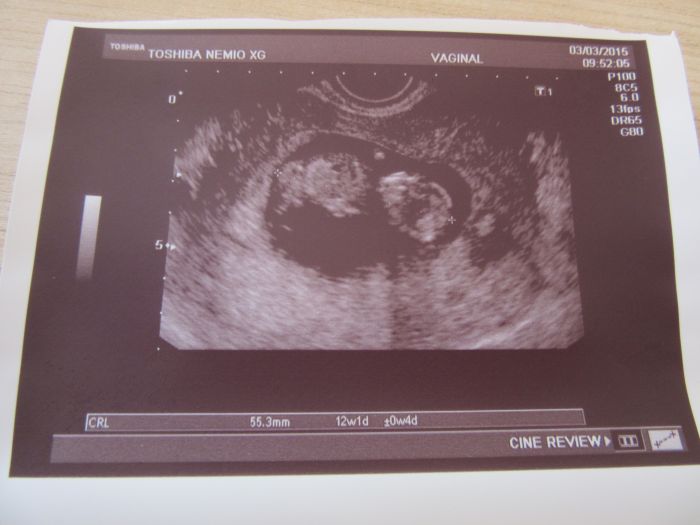

Ahoj holky, tak to dneska klaplo, jsem šťastná. Screening dopadl dobře, vše je v naprostém pořádku a za 14 dní se dozvím jak dopadla krev, pokud se jim něco nebude líbit tak se ozvou. Jinak mně vše ukázal i jak mám plný nacpaný žaludeček, to jsem teda koukala, nebude to zatím žádný divoch,jen trošičku se tam hýbal, ale moc tomu nedal. Jsem dnes 12+1 a měříme 5,53cm. Přikládám fotečky. Máme už hotové oznámení tak také přikládám fotečky hotového výrobku.

Kačko, gratulace, krása! Byl s tebou budoucí tatínek? A koukám, že na tom obrázku máš napsáno "vaginal" - to ti to dělali spodem? To muselo být něco, protože mě do toho břicha při vyšetření dost šťouchali a spodem bych si to nedovedla představit...